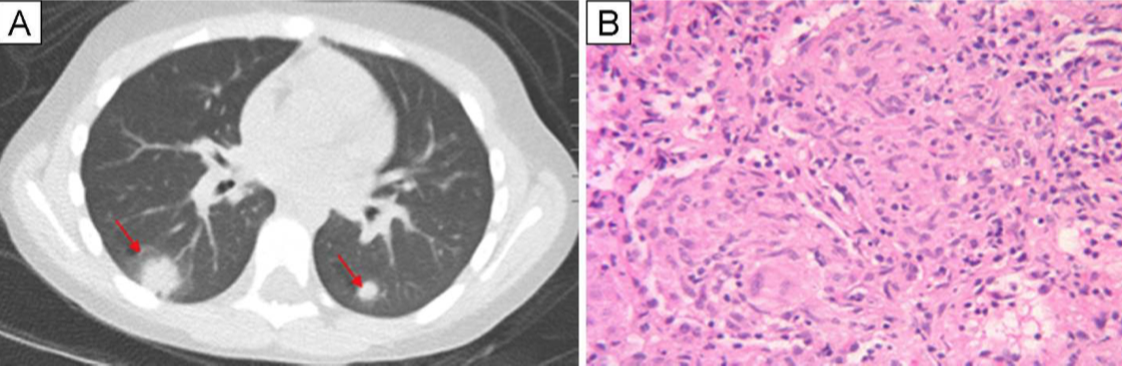

Computed tomography of the chest revealed pulmonary nodules with a halo sign and non-necrotizing granulomatous inflammation (Figure). Due to elevated creatinine in the setting of lung nodules, the patient underwent a renal and pulmonary biopsies (figures below)

Tubulointerstitial nephritis and uveitis (TINU). Renal biopsy revealed revealed marked acute tubulointerstitial nephritis with eosinophils. Lung biopsy revealed revealed non-necrotizing granulomatous inflammation, with negative staining for acid-fast bacilli and fungal organisms.